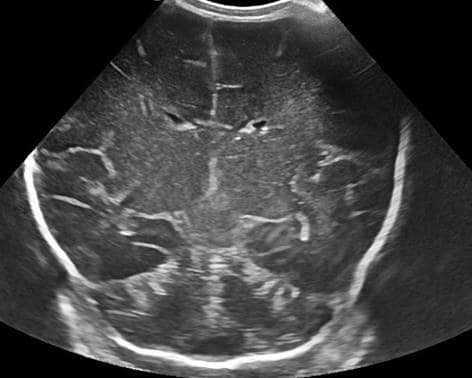

МРТ или УЗИ головного мозга при кисте

Ранее, когда в арсенале диагностических методов у врачей не было магнитно-резонансной томографии, диагностика кист головного мозга осуществлялась с помощью УЗ-энцефалографии. Такое исследование справлялось с выявлением кистозных образований у маленьких детей, но у взрослого пациента могло обнаружить только очень крупное новообразование.